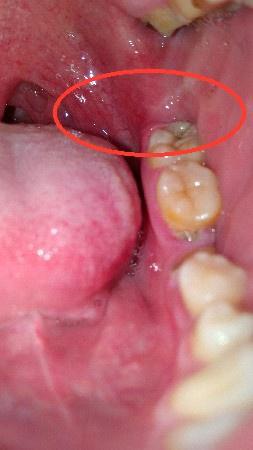

这是智齿冠周炎吗?

最开始左边牙齿最里面的那一颗有些不舒服,而后牙齿周边发疼,现在最里面的肉都非常疼,动嘴就疼。用药酒点了一下,更疼,舌头舔到好像起褶起

用手机开闪光灯拍了一下牙齿。图一图二,这样是智齿冠周炎吗?